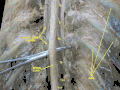

![]() The spinal cord shown in yellow extends through most of the length of the vertebral column to connect the brain with peripheral nerves. | |

The spinal cord is a long, thin, tubular structure made up of nervous tissue that extends from the medulla oblongata in the lower brainstem to the lumbar region of the vertebral column (backbone) of vertebrate animals. The center of the spinal cord is hollow and contains a structure called the central canal, which contains cerebrospinal fluid. The spinal cord is also covered by meninges and enclosed by the neural arches. Together, the brain and spinal cord make up the central nervous system.

In humans, the spinal cord is a continuation of the brainstem and anatomically begins at the occipital bone, passing out of the foramen magnum and then enters the spinal canal at the beginning of the cervical vertebrae. The spinal cord extends down to between the first and second lumbar vertebrae, where it tapers to become the cauda equina. The enclosing bony vertebral column protects the relatively shorter spinal cord. It is around 45 cm (18 in) long in adult men and around 43 cm (17 in) long in adult women. The diameter of the spinal cord ranges from 13 mm (1⁄2 in) in the cervical and lumbar regions to 6.4 mm (1⁄4 in) in the thoracic area.